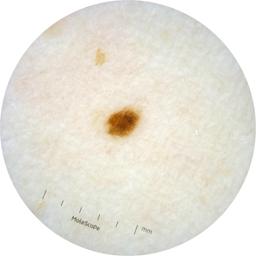

ISIC_2261268

acquisition_day 307

age_approx 50

anatom_site_1 Trunk

anatom_site_2 Posterior trunk

anatom_site_general posterior torso

diagnosis_1 Benign

diagnosis_confirm_type single image expert consensus

image_type dermoscopic